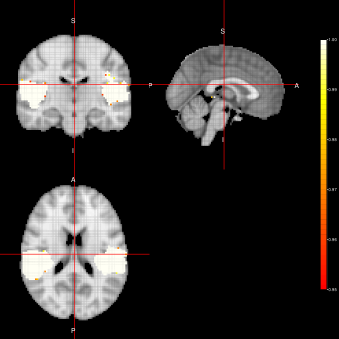

AG-algorithm(ACE-FEST) AG-algorithm(ACE-FFBS)

Refer to caption Refer to caption

AG-algorithm(ACE-FSTS)

Refer to caption

Figure 5: Activation Maps obtained for the ”voice localizer” example when using the AG-algorithm

In figure 5, we can see group activation maps obtained when using the AG-algorithm for every sampler option (FEST, FFBS, FSTS) at the individual level. From this example, we can conclude that with the AG-algorithm it is also possible to identify brain activation when analysing fMRI data for group activation.